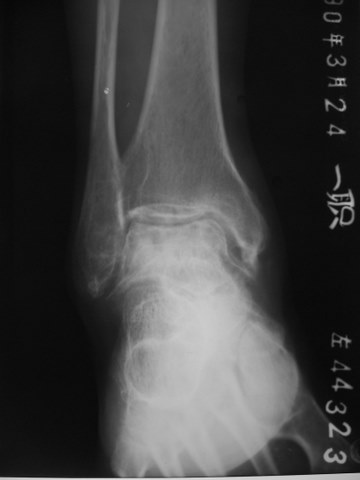

最近翻出一张刚上班时收藏的病例,男性,55岁,左踝部疼痛数年,加重2月余,正侧位片示:距骨塌陷变扁,密度增高,其内密度不均匀,关节面硬化毛糙,间隙变窄,跟骨短缩,诊断:踝关节改变符合大骨节病。

距骨塌陷变扁,密度增高,其内密度不均匀,关节面硬化毛糙,间隙变窄,考虑退行性骨关节病。

距骨扁,跟骨短,典型大骨节病。

大骨节病与别的骨关节病比较重要的区别是跟骨会有病变,但这个跟骨好像无异常,不太支持大骨节病,需流行病学支持。

这是我们这的地方病,很常见,西北地区,渭北,咸阳地区(永寿、麟游、礼泉等)都是高发区,跟骨外形变短,足弓略扁平,距骨改变是大骨节病成人型的典型表现,诊断上结合病人的居住史、饮水水质等不难做出诊断。